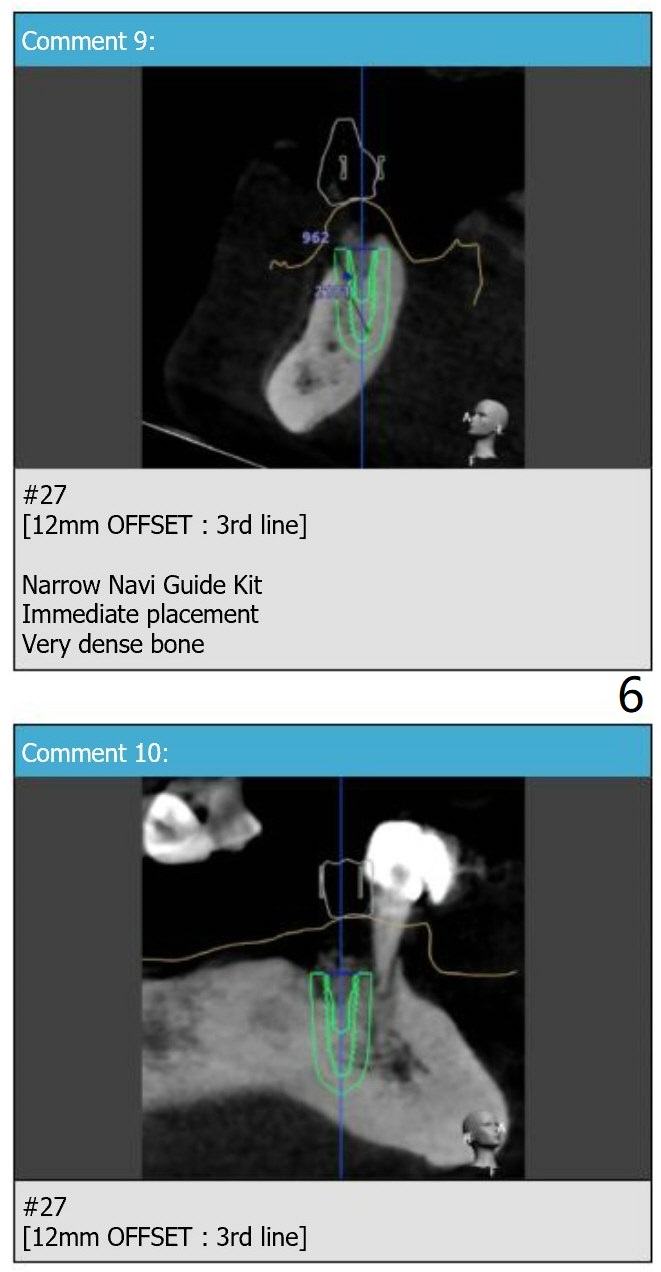

For placement of implants at #20, 22 and 27.

Lower Arch

Immediate Implant,

Trajectory,